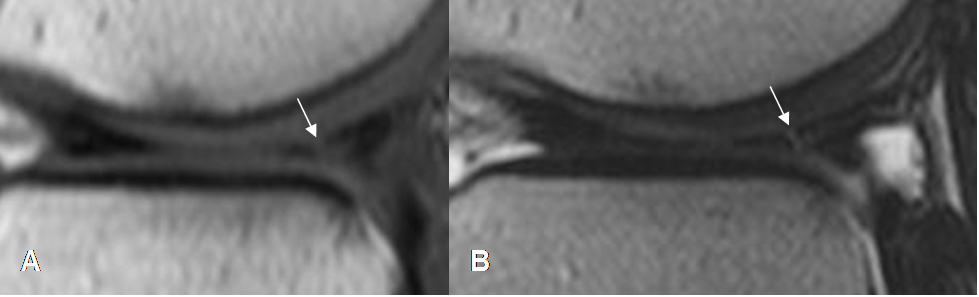

Fig 68. Ruptura meniscal dudosa.

A y B: RM sagital en T1. Imágenes hiperintensas y en sentido oblicuo, sobre el cuerno posterior del menisco interno. La completa comunicación con el borde inferior, es difícil de determinar con certeza.